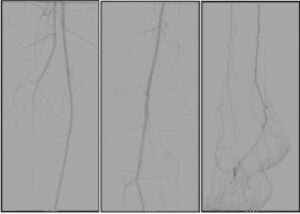

3-Yuxarı və aşağı ətrafların,həmçinin ayaq arteriyalarının angioqrafiyası